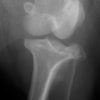

術前側面像

術前正面像

術前に25°であったTPAは、TPLO実施により7°に矯正されました。症例の歩行状態は良好です。